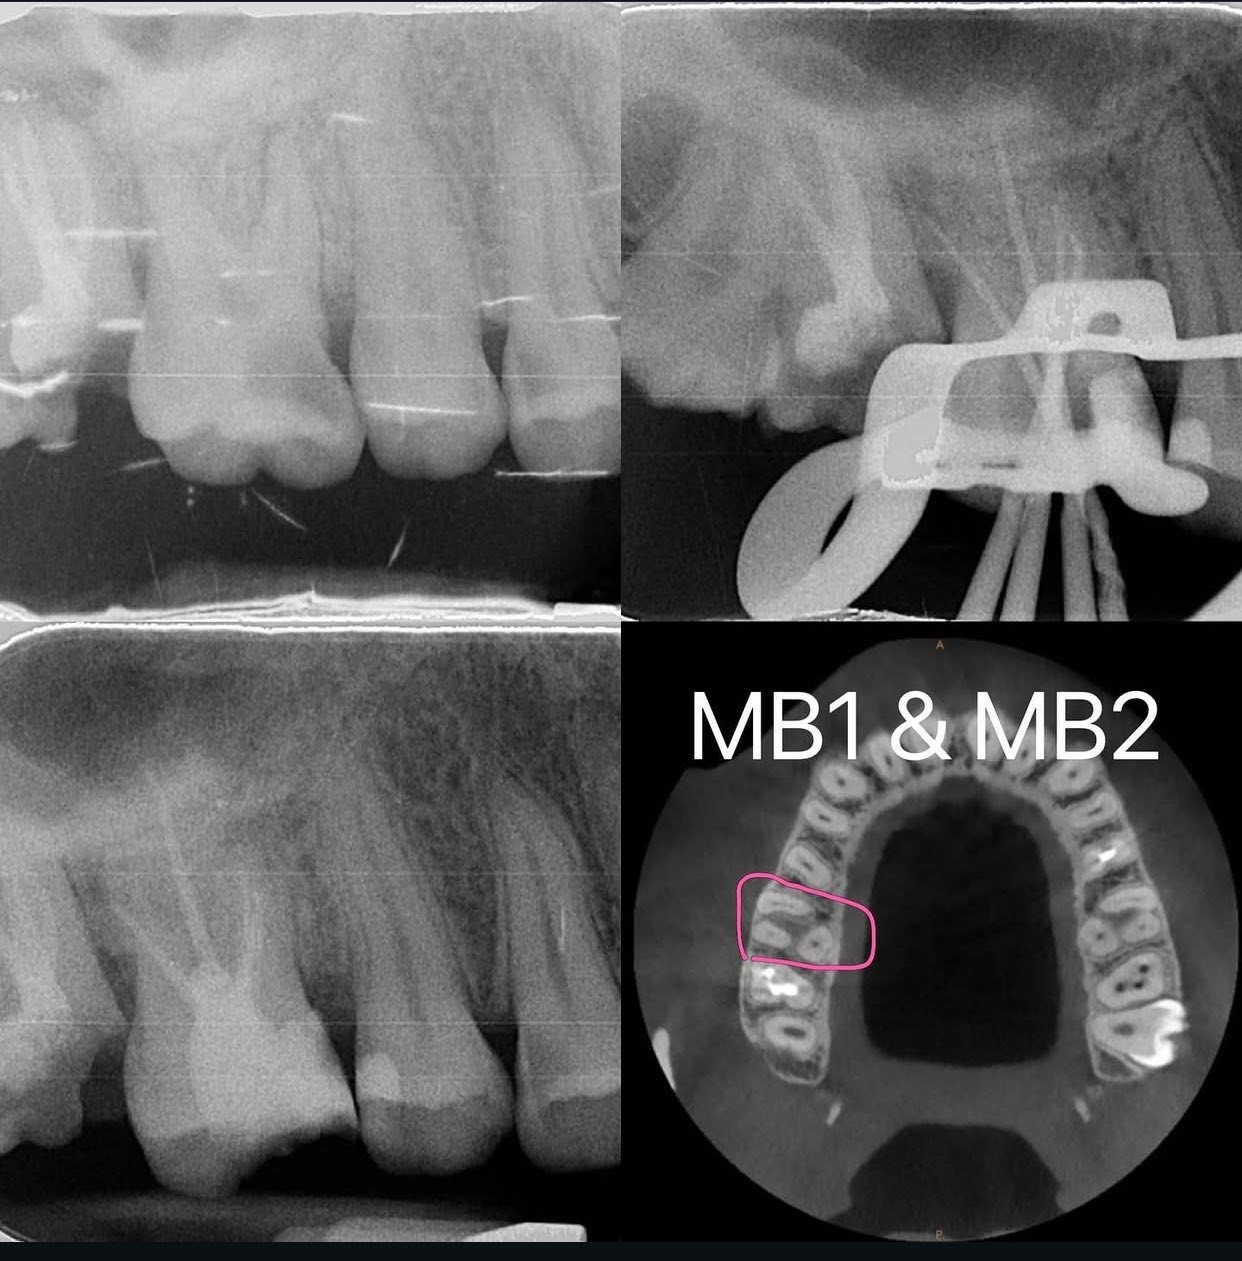

如何找到MB2呢?

常常上面大臼齒的近心頰側牙根會有第二根管,在做根管治療時能夠找到它可以提高根管治療的成功率,以下分享百謙院長找此根管的心得:

1. 從CT的橫切面看,看MB Root是否有兩個洞或狹長橢圓形。

2. 用牙科顯微鏡(放大工具)先把P和DB找到,然後在預設MB1位置(會在MB cusp 下方)的近心顎側找MB2(要看根管的紋路,會有溝紋和洞🕳️的樣態)。

3. 若MB1先找到,那將MB1與P連線,再將DB做一條線垂直此連線,就有機會在對側附近找MB2 。

(圖片部分來自簡院長的IG)